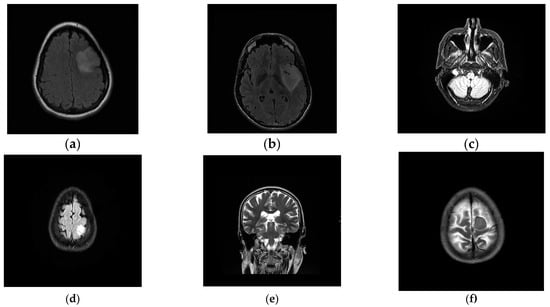

To verify the effectiveness of the proposed method, we randomly selected some images to test. For each brain tumor cross-sectional image, we compared the results of each algorithm with the results of manual segmentation. Figure 8 is the original image. Figure 9 shows the visualization results obtained by the proposed algorithm, CV, K-FCM [], Ostu [] and region growing algorithm [] for brain tumor segmentation. The experimental results of the threshold algorithm were obtained by manually adjusting the threshold parameters several times. Except for the algorithm in this paper, the other methods could not fully achieve automated detection and segmentation. From Table 2, we can observe the quantitative results of the four detection algorithms for brain tumor. When Accuracy, JSC and DSC were higher, it indicated that the prediction accuracy of the target was higher. The proposed method outperformed other algorithms on Accuracy, JSC, and DSC. Therefore, from the comprehensive analysis in Figure 9 and Table 2, it can be seen that the algorithm in this study had high accuracy in detecting and segmenting brain tumors. The proposed method has certain competitiveness compared with other classical algorithms, and is expected to provide a reliable reference for clinical decision-making. In addition, as is shown in Table 3, there are significant differences between the proposed model and other models.

Figure 8.

Examples of brain tumor images. (a) Test1. (b) Test2. (c) Test3. (d) Test4. (e) Test5. (f) Test6.